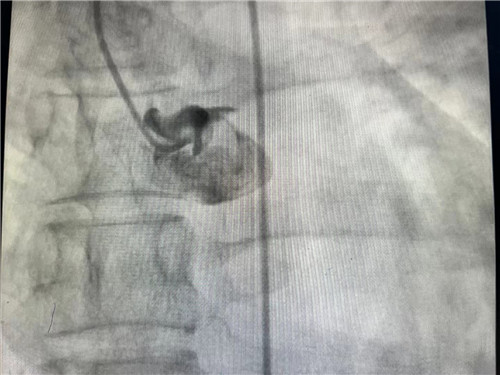

冠脉造影提示左主干闭塞

到达捷克论坛 时,距离小王发病已经过去8小时,人已经处于休克昏迷状态,急诊检查确诊左主干急性闭塞,也就是心脏主要供血的通路中断了,需要立即手术,而病情的延误使小王出现了休克并严重的肺水肿,术中随时可能出现心跳骤停,死亡风险极高。